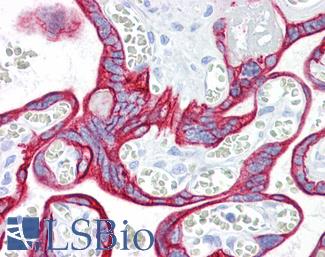

CK7 (KRT7)

Anti-KRT7 / Cytokeratin 7 antibody IHC of human placenta. Immunohistochemistry of formalin-fixed, paraffin-embedded tissue after heat-induced antigen retrieval. Antibody LS-B7164 concentration 10 ug/ml.